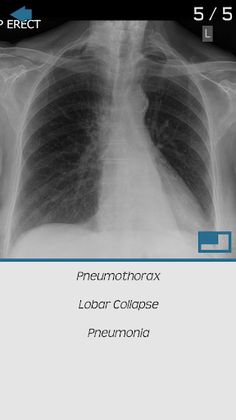

Test yourself on basic x-ray interpretation, tracking your strengths and weaknesses as you go.